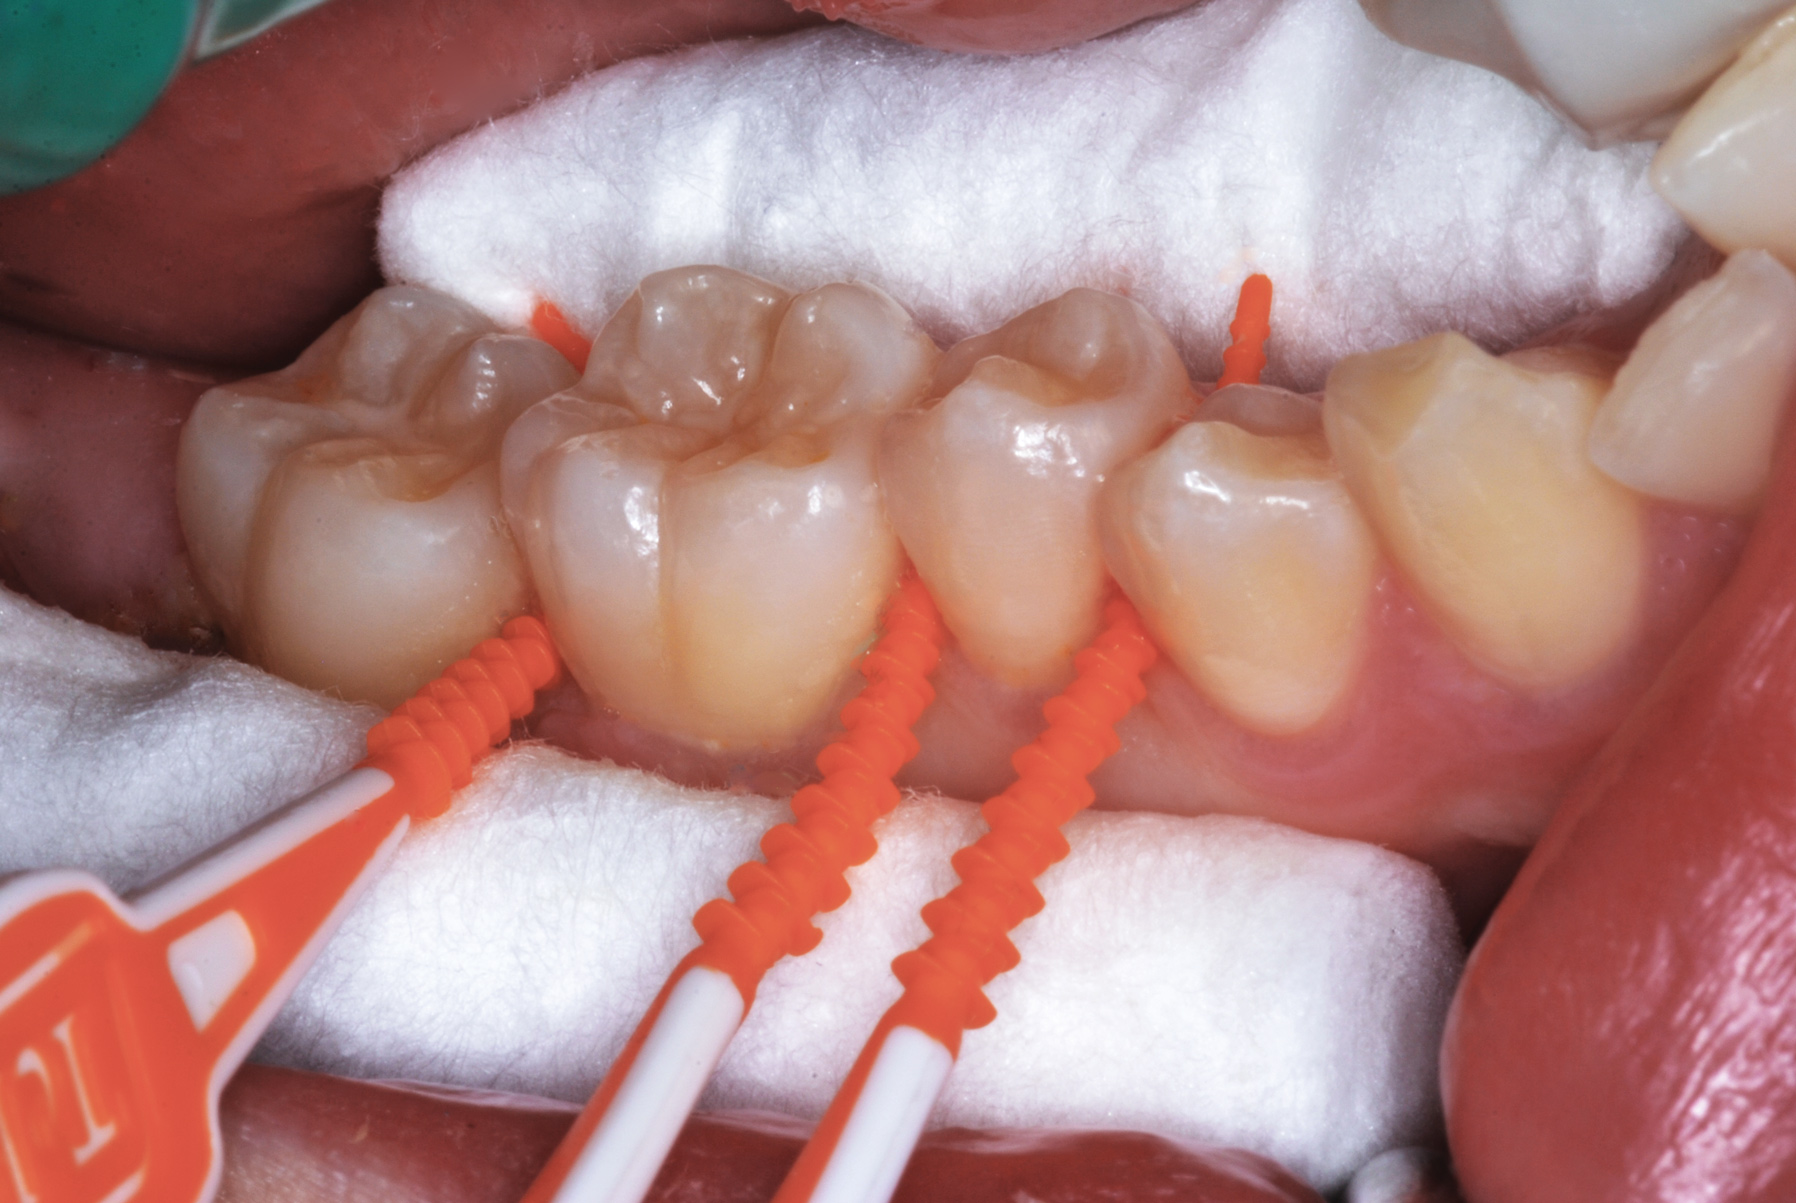

Interproximal insertion of SDF is demonstrated in different patients in Figure 3 through Figure 11. Various diameters and brands of soft dental picks may be used depending on the closeness of the proximal surfaces and ease of insertion; for example, some picks are designed for use in wider spaces between teeth. This protocol also offers versatility. Figure 3, for example, shows the simultaneous use of three thin soft dental picks to saturate proximal surfaces with SDF in a teenaged patient; the treated regions were subsequently covered with fluoride varnish (Figure 4). This patient was initially treated in April 2019 (Figure 5), with an identical re-application 3 months later. As shown in Figure 6, the December 2019 bitewing film revealed good results with the possible exception of the contact regions of the maxillary first and second molars. New SDF application was completed in the December appointment.

Fig 3. Three thin soft dental picks were used simultaneously for SDF proximal surface saturations in a teenaged patient (Fig 3). After 60 seconds, the treated regions were covered with 5% fluoride varnish (Fig 4). A comparison can be seen of pre-SDF-treatment bitewing films (Fig 5) and 8-month post-SDF bitewing films (Fig 6) for the patient shown in Fig 3 and Fig 4. Radiolucencies were similar or improved, except for contact of maxillary first and second molars.

Figure 3